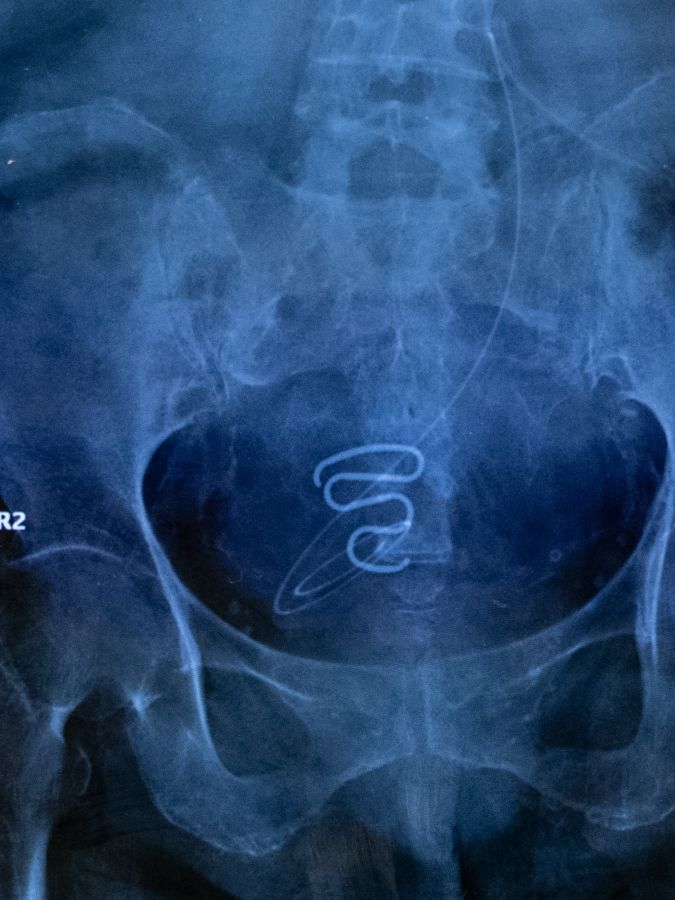

Contraceptions forcées au Groenland : la fin d’un secret

De 1966 à 1975, des milliers d’Inuites, souvent mineures, se sont vu poser de force un stérilet. La photographe Juliette Pavy a recueilli leur histoire.